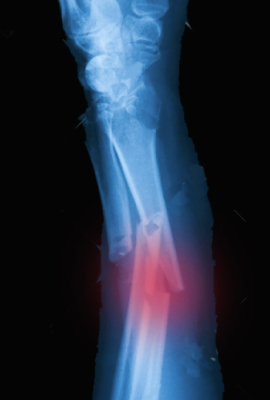

Tratamiento mediante cirugía o yeso (fibra de vidrio) de fracturas.